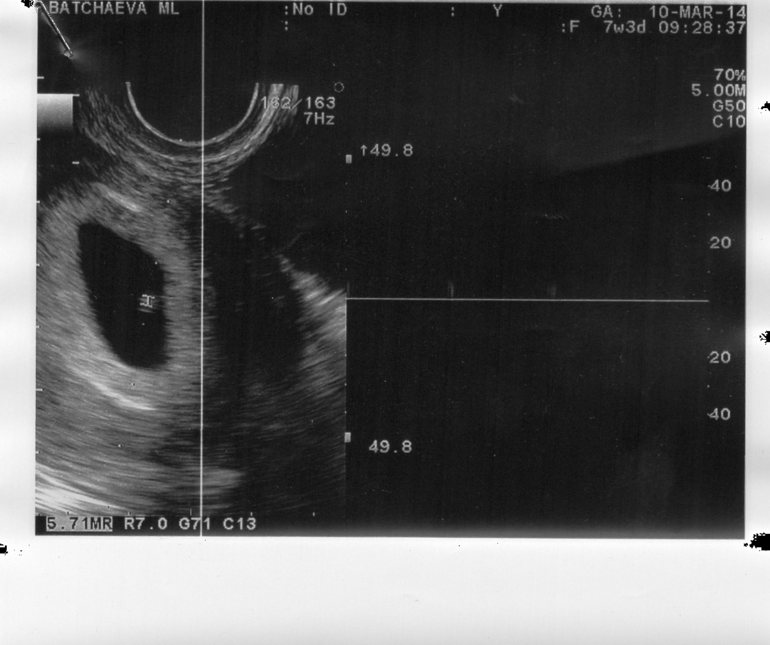

Вопросы про УЗИ, обследования и анализы: что, где, как, когда?Привет девчули. Сил моих больше нет. Сходила к лучшему узисту. Сказала ему что хгч 16 апреля был всего 25 потом стал расти. Он говорит 6 недель. По плодному так же получается. Свд 1,5 мм. И нашёл что то похожее на эмбрион. Сказал чистку не надо пока делать. Подождать ещё неделю. Что анэмрионию не ставят до 7 недель. Вот фото

У меня такая же фотка была 5 нед и 2 дня. Один в один, пятно. Нам уже 33 нед так что поздрвляю, мамочка!

Вот один в один картинка как у меня была, когда мне вместо сына анембрионию диагностировали. Еще неделька и услышишь сердечко.

Я ходила на узи 5 эмбриональных, было только плодное яйцо. в 7 эмбриональных только появился эмбрион и сердцебиение. А по месячным это была уже девятая неделя, то есть полных два месяца! Верьте и дай Бог , чтобы исход был благополучно для Вас!💐